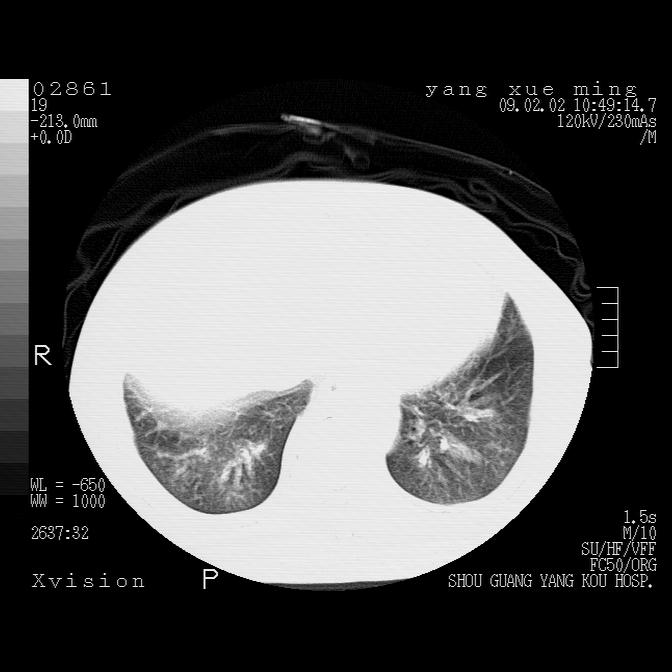

以下是引用zbp537在2009-2-3 19:08:00的发言:[br]我诊断为肺泡性肺水肿。[br]诊断依据:[br]1、心影普遍增大,肺血管增粗,并见絮状高密度影,肺门改变显著。[br]2、临床上表现胸闷咳嗽,无发烧,不是一个典型的肺部感染的病史。

以下是引用lkc8963在2009-2-3 20:11:00的发言:[br]1)右上肺陈旧病灶。2)右下肺团块及团片影,影像表现符合感染。3)左心增大,左冠脉钙化,符合冠心病。4)双侧肺门扩大,以左侧为著,肺动脉干略粗,左上肺局限性气肿,为谨慎起见,需除肿瘤,建议增强。

以下是引用lkc8963在2009-2-3 20:11:00的发言:[br]1)右上肺陈旧病灶.2)右下肺团块及团片影,影像表现符合感染.3)左心增大,左冠脉钙化,符合冠心病.4)双侧肺门扩大以左侧为著,肺动脉干略粗,左上肺局限性气肿,为谨慎起见,需除肿瘤,建议增强.